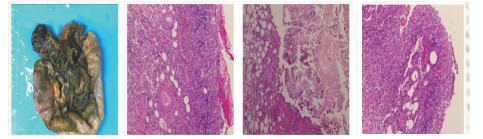

| 图 3 腹腔镜探查+坏死空肠切除+大网膜切除+肠系膜上动脉探查+空回肠双腔造口术后病理(2018-1-19):可见部分肠壁全层坏死,合并慢性炎症,肉芽组织增生 |

1 资料与方法患者男,30岁,因“腹胀、腹痛6 d,高热1 d”于2017年12月11日由广州南沙区中心医院转诊收入中山大学孙逸仙纪念医院全科医学科。患者本次起病前无明确病因或明显诱因。患者以左上腹轻微胀痛起病,进行性加重。南沙区医院查血常规:白细胞14.27×109/L,血小板50×109/L,中性粒细胞比例74.5%,嗜酸粒细胞1.02×109/L,嗜酸粒细胞比例7.2%。全腹CT+CTA提示:门静脉左右主干及其小分支栓子形成。后在3 d内连续复查血常规,提示血小板进行性下降,由50×109/L相继降至35×109/L、18×109/L;(嗜酸粒细胞计数及比例未能提供),并出现高热(体温39.5℃),因病情危重,遂转诊本院。入院时患者精神疲乏、高热,腹部胀痛难忍,伴有咳嗽。查体:体温38.6℃,心率87次/min,血压102/76 mmHg,指尖血氧饱和度90%~91%。双肺呼吸音粗,双肺均可闻及小水泡音。腹部稍膨隆,叩诊鼓音,左上腹及脐周轻压痛,无反跳痛。听诊肠鸣音减弱,约1~2次/min。当天查血常规示白细胞11.85×109/L,血小板23×109/L,中性粒细胞比例58.1%,嗜酸粒细胞3.5×109/L,嗜酸粒细胞比例29.5%。凝血常规提示:PT 15.9S,PTA 51.1%,PT/R 1.39,Fbg 1.59 g/L,PTINR 1.39,APTT 35.2 s,D-二聚体114.36 mg/L FEU(参考值范围0~0.55 mg/L FEU)。胸部+全腹部CT+CTA示“门静脉主干及左、右支、肠系膜上静脉近端栓子形成;腹主动脉及左侧髂总动脉小附壁血栓;左肺上叶尖后段、左肺上叶下舌段、右肺中叶及双肺下叶炎症;乙状结肠两段节段性管壁增厚,建议排外占位性病变;腹水、盆腔积液,大网膜炎性病变可能性大”。每日复查血常规,发现血小板进行性下降,最低至15×109/L(参考值范围125~350×109/L),嗜酸粒细胞计数及比例进行性升高,分别达到8.07×109/L(参考值范围0.020~0.52×109/L)和51.1%(参考值范围0.4-8.0%)。每日复查凝血常规亦提示凝血指标不断恶化,纤维蛋白原最低降至0.63 g/L。在予禁食、“美平(美罗培南)”抗感染、输注纤维蛋白原及血小板、维护水电解质平衡及营养支持的积极治疗的同时,还积极完善了以下检查寻找病因:①血液系统方面:血浆鱼精蛋白副凝实验:阳性(+);凝血功能实验:PT 15.5S↑,PTA 47.8%↓,PT/R 1.35↑,PTINR 1.36↑,APTT 40.4 s↑,AT-Ⅲ 57.7%↓,F-VII 32.8%↓,F-Ⅷ 68.1%↓,F-X 68.0%↓,F-XII 24.0%↓;纤维蛋白降解产物:381.4 mg/L↑;血栓弹力-血小板图:R时间10.3 min↑;角度18.5度↓;最大血块强度13.2 mm↓;MA(ADP)值5.6 mm↓。骨髓病理学:嗜酸性粒细胞增多(43%),巨核细胞减少(7个)。慢淋/淋巴瘤表型分析:获取和分析细胞数5.0万;粒细胞区百分比82.6%;淋巴细胞区百分比9.4%;单核细胞区百分比2.0%;CD45dim细胞区百分比1.3%;有核红及细胞碎片区域百分比4.6%。ETV6/PDGFRB融合基因、FIP1L1/PDGFRA融合基因(—)。骨髓细胞学病理结果:符合嗜酸细胞增多症;②消化系统检查:大便细菌培养鉴定及药敏提示无志贺、沙门菌生长,有真菌生长;大便难辨梭菌毒素检测(—);粪便找寄生虫、找阿米巴、寄生虫七项均为(—);消化肿瘤系列提示CA-125 244.8 U/mL↑;腹腔穿刺术穿出“血性腹水”,腹水CA-125 1006.0 U/mL↑,腹水找癌细胞(—);复查腹部CT+CTA:乙状结肠两段节段性管壁增厚,建议进一步检查;排外占位性病变;遂行PET-CT:提示全身未见明确恶性征象。行电子结肠镜示:内镜诊断:(1)回肠末段炎症;(2)乙状结肠炎症;(3)内痔。钳取组织送病理,提示:标本①(回肠末端)黏膜组织呈慢性炎,伴糜烂,一些嗜酸性粒细胞浸润(约35个/HPF);②(乙状结肠)黏膜组织呈慢性炎,伴糜烂,个别嗜酸性粒细胞浸润(约4个/HPF)。③风湿免疫系统方面:免疫八项、风湿四项:C反应蛋134.0 mg/L,余未见异常;总IgE 170 IU/mL↑;抗ENA抗体、狼疮两项、血管炎两项、免疫球蛋白G4、抗心磷脂抗体三项均为阴性;④其他感染病原学检查:乙肝、肝炎系列、性病三项、痰找抗酸杆菌、T-spot实验、流行性出血热、登革热抗体、登革热病毒NS1抗原、外斐氏试验、肥达氏试验、痰结核培养、骨髓培养、血液细菌、血液厌氧菌培养均为阴性。经过上述检查,初步考虑“特发性嗜酸性细胞增多症”,于12.15开始予“甲泼尼松龙40 mg静滴, 1次/d”及“低分子肝素0.6 ml皮下注射, 1次/d”抗炎抗凝治疗。患者病情及检验指标有所好转,热退、腹胀减轻,血常规提示血小板升至49 ×109/L,嗜酸粒细胞计数和比例均下降至正常,凝血常规提示D-二聚体降至47.90 mg/L FEU。但12-22患者自行进食多量米饭后突发腹胀痛较前加重,急查血常规提示白细胞升至21×109/L,血小板再次下降至15×109/L,D-二聚体升至97.28 mg/L FEU,全腹CTA提示“门静脉主干及左、右支、肠系膜上静脉近端新发栓子形成”,遂于当日转至ICU予“尿激酶20万U+肝素钠1250 U”溶栓治疗后予“低分子肝素0.6 ml皮下注射, 1次/12 h”序贯抗凝治疗。后患者病情渐渐稳定,至2018-1-18患者在“甲泼尼松龙12 mg口服, 1次/d”及“立伐沙班20 mg口服, 1次/d”的维持治疗下,血小板、嗜酸粒细胞计数及纤维蛋白原均回复正常,D-二聚体下降至3.52 mg/L FEU。但遗憾的是,此时患者再次进食大量米饭,约1 h后突发腹痛、气促,急行胸片+腹平片提示:“双侧膈下游离气体,考虑胃肠道穿孔可能;双下肺少许炎症,少量胸腔积液;腹部多量积气伴肠腔扩张”。遂即送手术室行全麻下“腹腔镜探查+坏死空肠切除+大网膜切除+肠系膜上动脉探查+空回肠双腔造口术”,术后病理提示标本①(大网膜)脂肪组织,部分坏死,合并慢性炎,伴一些中性粒细胞浸润,较多泡沫样组织增生,未见明确血栓,未见恶性改变。②(部分空肠)肠壁组织,部分肠壁全层坏死,合并慢性炎,肉芽组织增生,未见明确血栓,未见恶性改变。免疫组织化学:CD38浆细胞(+)、IgG(+)、IgG4(﹣)。术后继续予“立伐沙班10 mg/d”和“甲泼尼松龙8 mg/d”口服治疗,并于2018.2.4停用“甲泼尼松龙”。2.28复查全腹CTA,仍可见“脾静脉新发血栓,门静脉及肠系膜上静脉血栓较前好转”。3.20行空回肠双腔造瘘管泛影葡胺造影术提示“双腔造瘘管通畅,右中下腹小肠蠕动尚可,结肠各段及直肠通畅,未见对比剂外漏征象”。但患者合并了严重的短肠综合征,致严重低钾低钠血症和继发的代谢性脑病,病情再度转危。继续纠正电解质紊乱、补充营养,最终病情好转后于4.11行“造瘘口回纳修补术”。随访半年,患者仍口服“立伐沙班10 mg/d”抗凝治疗,复查血常规、凝血常规等各项指标均正常,但营养状况较差。